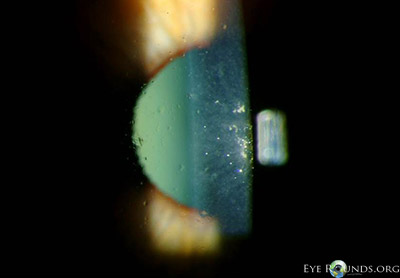

• Cornea: Polymorphous glass like deposits in the deep corneal stroma OU

Figure 1: Slit Lamp Photos (click on image for higher resolution)

Based on the clinical appearance and asymptomatic nature of her corneal opacities, the patient was diagnosed with polymorphic amyloid degeneration.

The diagnosis is made by slit lamp examination, which reveals gray-white axial deep stromal opacities of the cornea. Clear, refractile, stromal filamentous opacities are evident by retroillumination [7].